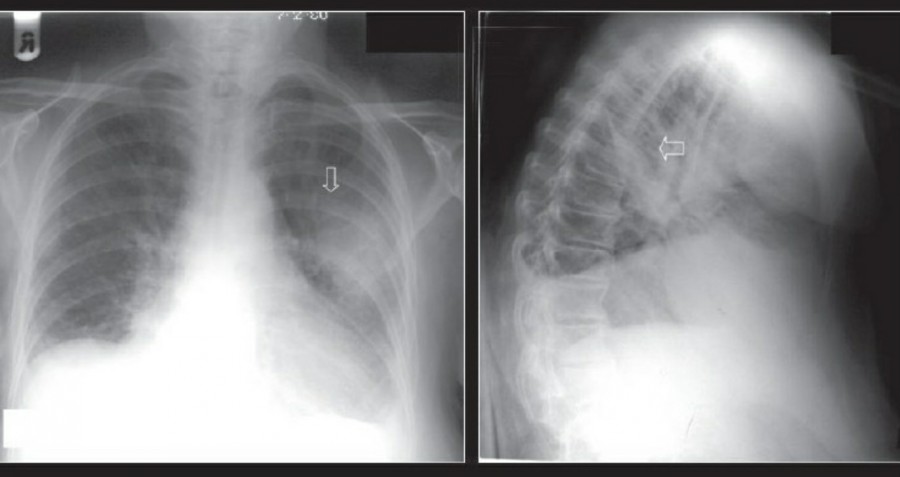

공기는 nondependent position으로 위치하므로, X ray상에서는 환자 자세에 따라 다르게 나타난다. Erect position에서 공기는 lung의 apicolateral surface에 위치하고 얇고 하얀 pleural line이 나타나며 그 뒤로 lung marking이 보이지 않는다.

하지만 pleural line 뒤로 lung marking이 존재한다고 해서 pneumothorax를 배제할 수 없다. Pneumothorax의 진단은 특히 parenchymal disease가 있을 때 진단하기 힘든데, 이는 compliance의 변화 때문에 collapse가 잘 안 되기 때문이다. Skin fold가 pneumothorax와 비슷하게 보이기도 한다.